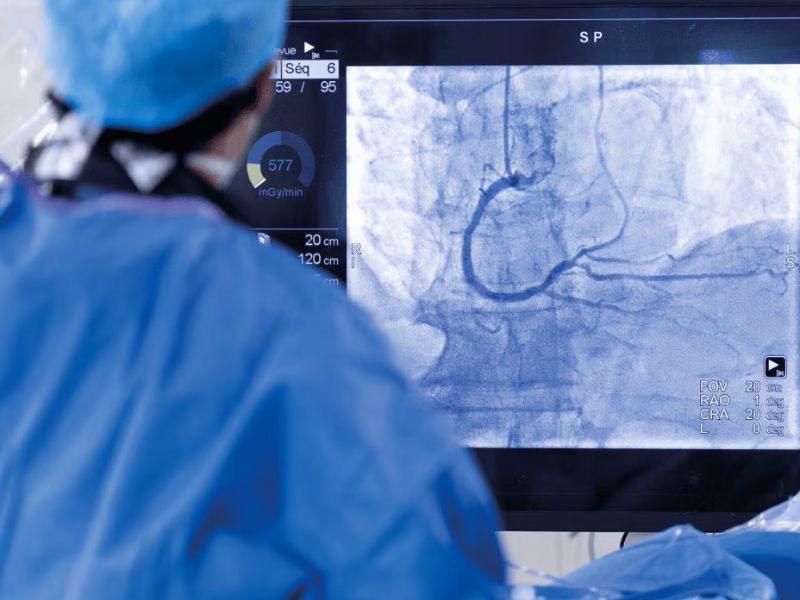

Ahora bien, estos procedimientos se hacen generalmente en un laboratorio de cateterismo cardíaco, también conocido como sala de hemodinamia, que cuenta con tecnología médica que ofrece una visualización excelente del corazón y de sus cavidades. Además, estos equipos, integran sistemas diseñados para proporcionar imágenes con la claridad necesaria[9] y por si fuera poco, recientemente se han incorporado sistemas avanzados de imagenología con Inteligencia Artificial (IA) para apoyar al personal médico en el diagnóstico y tratamiento en tiempo real de enfermedades cardiovasculares y otras afecciones[10].

Algunas de las afecciones que se pueden atender a través de la cardiología intervencionista mínimamente invasiva son: la cardiopatía coronaria y el infarto de miocardio mediante angioplastias y catéteres para abrir arterias bloqueadas o restablecer el flujo sanguíneo[7]. También, esta especialidad se emplea en trombosis y embolias para extraer coágulos[8].